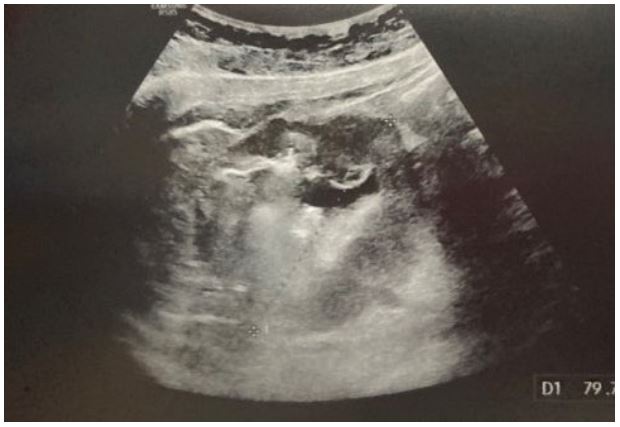

She repeated an upper GI endoscopy (Figure 1), which was completely normal without any sign of recent blood loss and was scheduled for ileo-colonoscopy and a video capsule endoscopy. In her diagnostic workup, we decided to perform an abdominal ultrasonography that revealed a giant mass measuring approximately 8-9 cm in the epigastric region, inferior and posterior to the liver. The lesion was composed of liquid and gas, featured a thickened wall measuring between 10 to 18 mm (Figure 2). All other abdominal organs appeared normal.

Figure 2: Abdominal ultra-sound with the evidence of the mass.